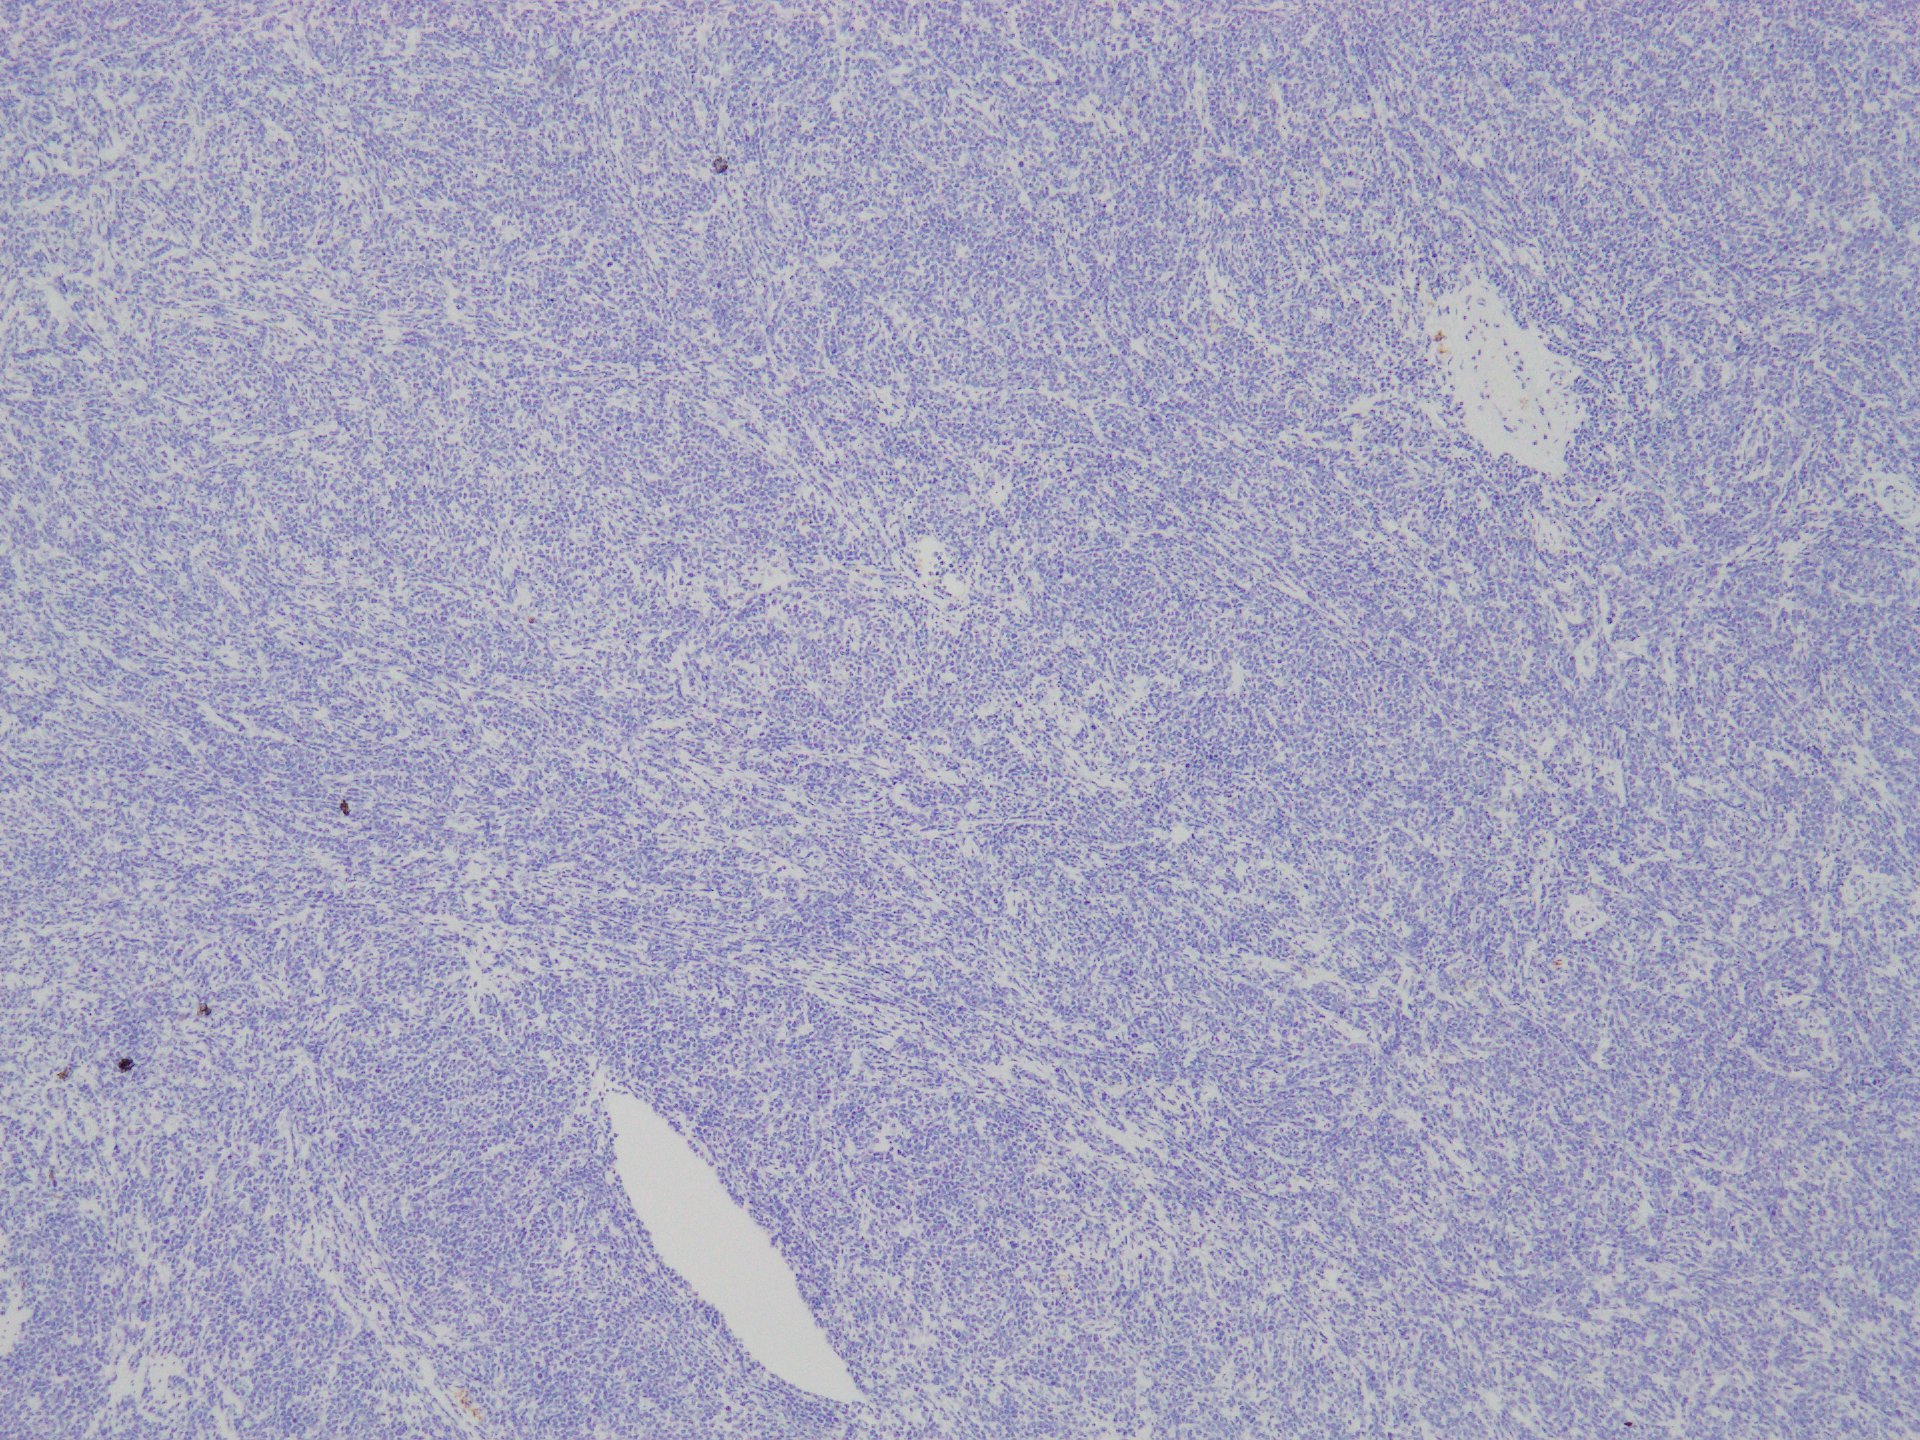

CD30

granzyme B

CD56

c-KIT(CD117)